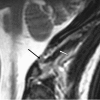

Background: This paper describes MRI findings of upper cervical subluxation due to alar ligament disruption following a vehicular collision. Incidental findings included the presence of a myodural bridge and a spinal cord syrinx. Chiropractic management of the patient is discussed.

Case presentation: A 21-year old female presented with complaints of acute, debilitating upper neck pain with unremitting sub-occipital headache and dizziness following a vehicular collision. Initial emergency department and neurologic investigations included x-ray and CT evaluation of the head and neck. Due to persistent pain, the patient sought chiropractic care. MRI of the upper cervical spine revealed previously unrecognized clinical entities.